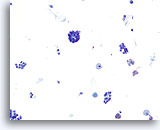

Negatief voor maligne cellen consistent met Hashimoto-thyroïditis

Wij zijn er achter gekomen dat ThinPrep niet optimaal is voor de diagnose van thyroïditis.[6] Hashimoto-thyroïditis wordt gekenmerkt door lagen of groepen folliculaire cellen met variërende mate van Hürthle-celveranderingen op een achtergrond van variërende aantallen lymfocyten en plasmacellen met incidenteel lymfoïde en folliculaire kernaggregaten. Omdat lymfocytisch/Hashimoto-thyroïditis een veelvoorkomende bevinding is bij de schildklier, is de monsterverzameling essentieel bij het uitsluiten van andere eveneens voorkomende en meer belangrijke laesies.